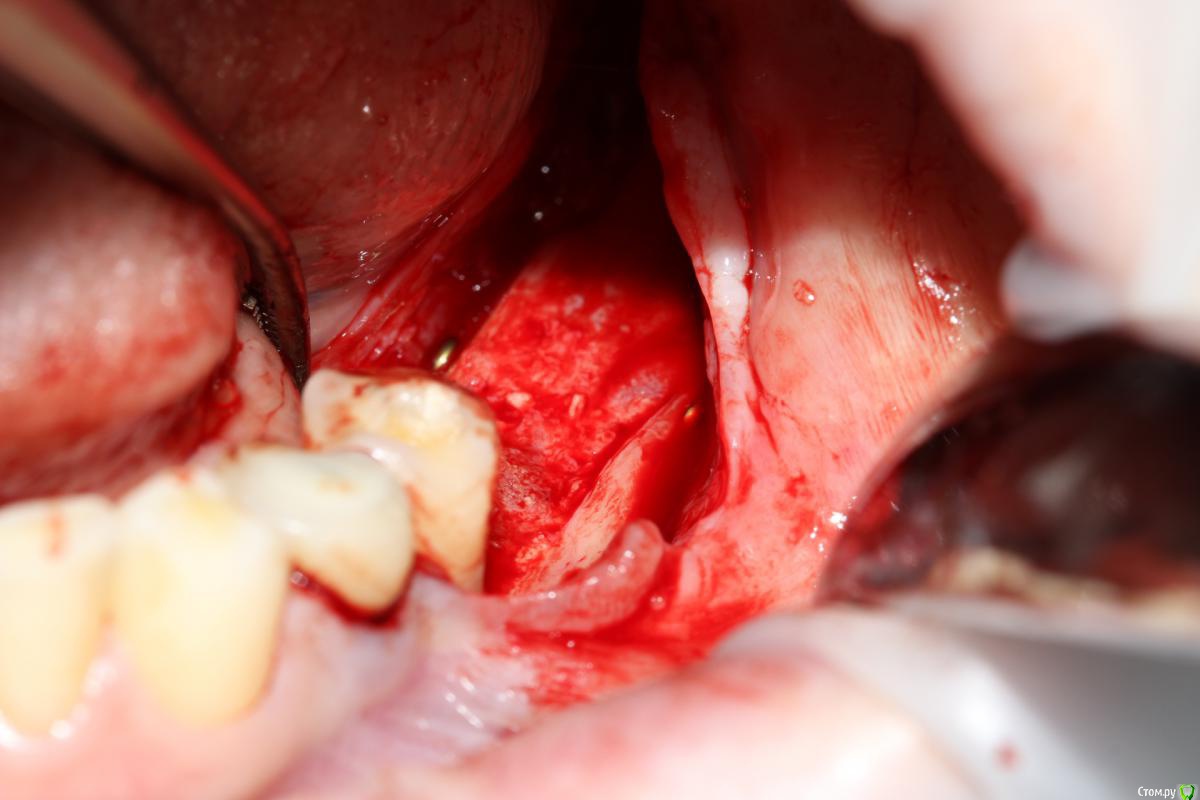

Популярный пост Dantist55 Опубликовано 22 декабря, 2014 Автор Популярный пост Поделиться Опубликовано 22 декабря, 2014 Через 5 месяцев... 21 Ссылка на комментарий

SDC Опубликовано 22 декабря, 2014 Поделиться Опубликовано 22 декабря, 2014 Через 5 месяцев...Мне не понравилось просветление в 3 квадранте. Крутили КТ? Что это? Ссылка на комментарий

Dantist55 Опубликовано 22 декабря, 2014 Автор Поделиться Опубликовано 22 декабря, 2014 Мне не понравилось просветление в 3 квадранте. Крутили КТ? Что это?Перед имплантацией крутил-все было норм. Ссылка на комментарий

SDC Опубликовано 22 декабря, 2014 Поделиться Опубликовано 22 декабря, 2014 Перед имплантацией крутил-все было норм.Значит так эксклюзивно фонит. Ссылка на комментарий